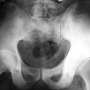

Tüm kanserler arasındaki görülme sıklığı yaklaşık %1'dir. Erkek / kadın oranı 1.5-2 / 1 dir. Genelde 10-30 yaşları arasında (%75) ve kemiklerin ekleme komşu uçlarında görülse de kemiğin herhangi bir bölgesinde ortaya çıkabilir. Giderek artan, istirahat ve ilaçla geçmeyen ağrı, sert, hareketli olmayan şişlik gibi şikayetler en sık rastlanan bulgulardır. Bir çok hasta, o bölgede daha önce herhangi bir darbe yaşandığını söylese de bu konuda herhangi bir bilimsel ilişki gösterilememiştir.

Tanı koyma aşaması dikkatli bir muayene ile başlar. Düz grafi (normal röntgen), osteosarkom teşhisinde çok önemlidir. Deneyimli bir hekim tarafından incelendiğinde röntgen çoğu zaman tanı için yeterlidir. Osteosarkom şüphesi bulunanbir hasta, mutlaka bu konuda uzmanlaşmış bir adrese yönlendirilmelidir, çünkü tanı için izlenecek yol ve yöntemler tedavi başarısı ile direkt ilişkilidir. Tüm vücut sintigrafisi, tümör bölgesinin MR incelemesi ve akciğerin BT tetkiki ile hastalığın lokal ve sistemik yayılımı değerlendirilir.